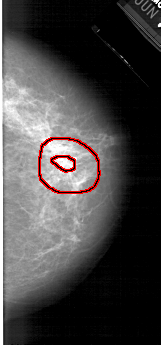

A_1424_1.RIGHT_CC

RIGHT_CC LINES 5161 PIXELS_PER_LINE 2401 BITS_PER_PIXEL 12 RESOLUTION 43.5 OVERLAY

FILE: A_1424_1.RIGHT_CC.OVERLAY

TOTAL_ABNORMALITIES 1

ABNORMALITY 1

LESION_TYPE MASS SHAPE IRREGULAR MARGINS SPICULATED

ASSESSMENT 5

SUBTLETY 3

PATHOLOGY BENIGN

TOTAL_OUTLINES 2

BOUNDARY

CORE